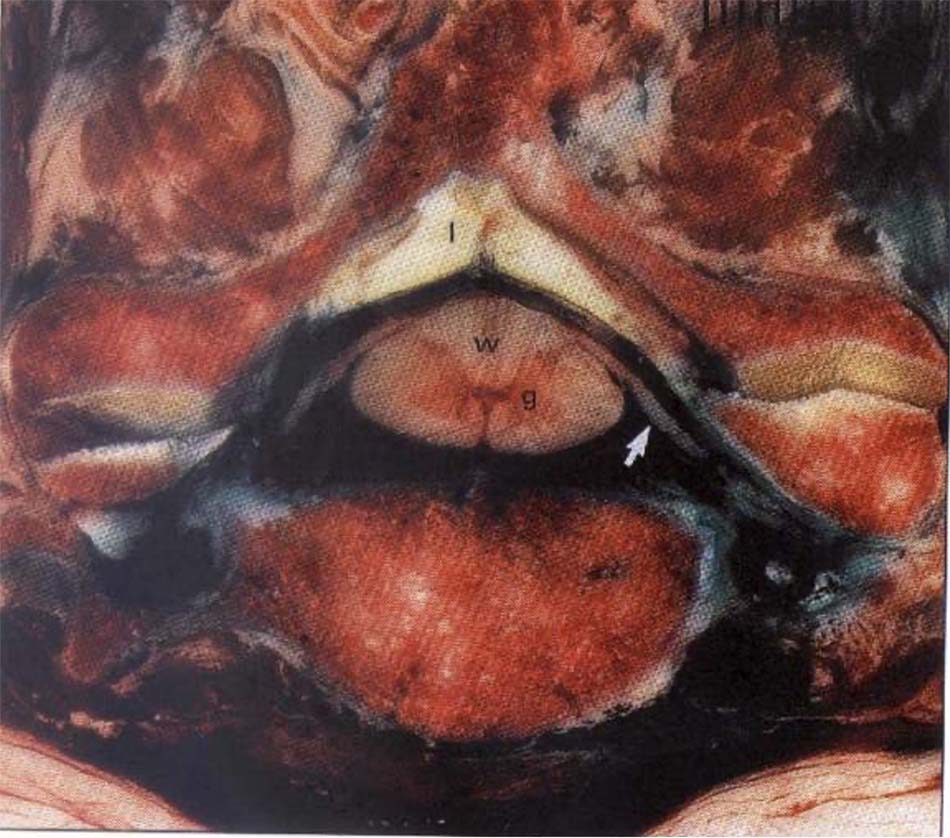

Là khớp giữa mỏm nha đốt trục với một vòng tròn do cung trước đốt đội và dây chằng ngang đốt đội [6] (là dải ngang của dây chằng chữ thập tạo nên).

Dây chằng hình chữ thập: gồm một dải chạy ngang, nối mặt trong của hai khối bên đốt đội gọi là dây chằng ngang và các bó dọc, nối bờ trên của dải ngang với xương chẩm và bờ dưới của dải ngang với đốt trục. Dây chằng hình chữ thập giữ cho mỏm nha áp vào mặt sau cung trước đốt đội và chia lỗ đốt sống của đốt đội làm hai phần. Phần sau chứa tuỷ sống, phần trước chứa mỏm nha. Mặt sau dây chằng chữ thập có màng mái từ mặt sau thân đốt trục chạy lên hoà lẫn với màng cứng của sọ não và là thành phần tiếp tục của dây chằng dọc sau [49]. Ở trước dây chằng ngang, mỏm nha được cố định bởi hai dây chằng: